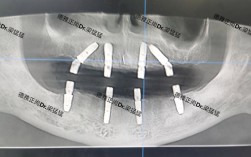

- 种植体周围X线片显示骨吸收: 这是诊断和评估严重程度的关键,可以看到种植体周围牙槽骨高度降低,形成“骨陷窝”。